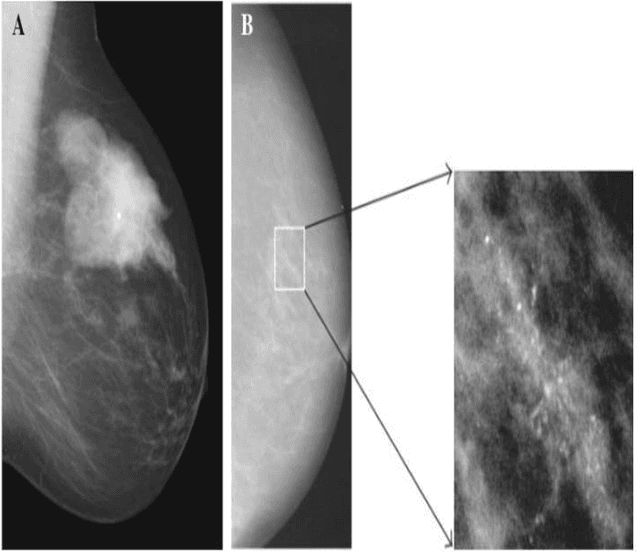

Abstract:Breast cancer is a common fatal disease for women. Early diagnosis and detection is necessary in order to improve the prognosis of breast cancer affected people. For predicting breast cancer, several automated systems are already developed using different medical imaging modalities. This paper provides a systematic review of the literature on artificial neural network (ANN) based models for the diagnosis of breast cancer via mammography. The advantages and limitations of different ANN models including spiking neural network (SNN), deep belief network (DBN), convolutional neural network (CNN), multilayer neural network (MLNN), stacked autoencoders (SAE), and stacked de-noising autoencoders (SDAE) are described in this review. The review also shows that the studies related to breast cancer detection applied different deep learning models to a number of publicly available datasets. For comparing the performance of the models, different metrics such as accuracy, precision, recall, etc. were used in the existing studies. It is found that the best performance was achieved by residual neural network (ResNet)-50 and ResNet-101 models of CNN algorithm.